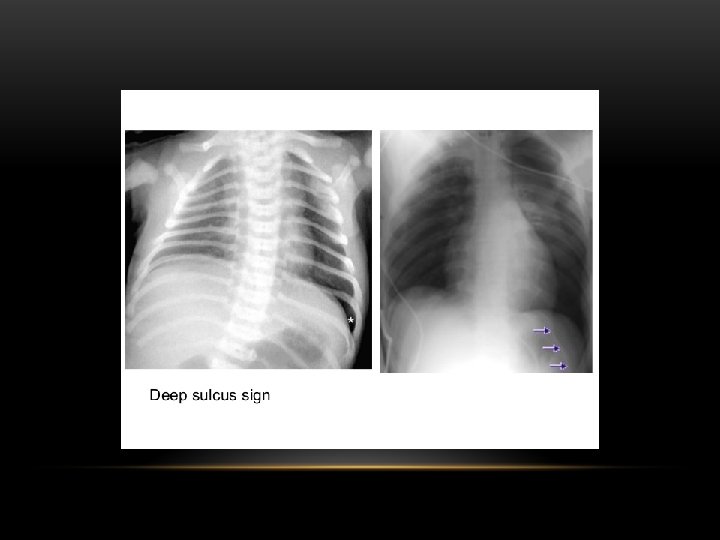

Pneumothorax is air in the pleural space. Radiological criteria: Air (black) in pleural space. No lung markings in pleural space. Recognition of atelectatic lung (lung margin). The lung recoils to a resting state as the negative pressure in the pleura is lost (relaxation atelectasis).

Shift of mediastinum to the opposite side. The mediastinum is held in the middle by balance between pleural pressures. When the negative pressure on the side of the pneumothorax is lost, the mediastinum gets pulled by the normal negative pressure from the opposite side. Progressive shift subsequently could result from a push secondary to tension pneumothorax. Opposite lung gets the entire cardiac output and the vascular markings become prominent.

Tension pneumothorax : is the progressive build-up of air within the pleural space, usually due to a lung laceration which allows air to escape into the pleural space but not to return. Positive pressure ventilation may exacerbate this 'one-way-valve' effect. Progressive build-up of pressure in the pleural space pushes the mediastinum to the opposite hemithorax, and obstructs venous return to the heart. This leads to circulatory instability and may result in traumatic arrest.

Tension Pneumothorax • No vascular markings on right • Shift of mediastinum to left • Atelectasis right lung • Increased haziness on left: Diversion of entire cardiac output